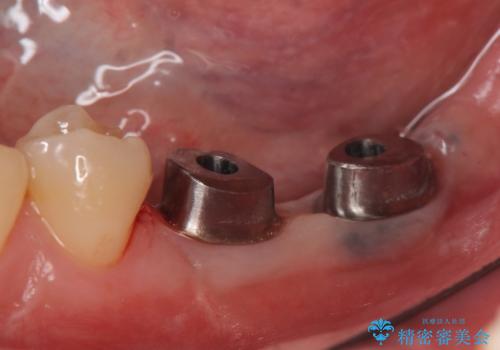

左下にインプラント(ストローマン)を2本埋入し、オールセラミッククラウンによる補綴を行いました。

当院では主にストローマンという種類のインプラントを治療に用いています。

ストローマンは世界的にもNo1のシェアを誇り、骨との適合にも優れたインプラントです。

カスタムアバットメントは患者様それぞれの歯茎に合わせて製作されたオーダーメイドのアバットメントです。

既製のアバットメントに比べ適合がよく、高い清掃性を誇ります。